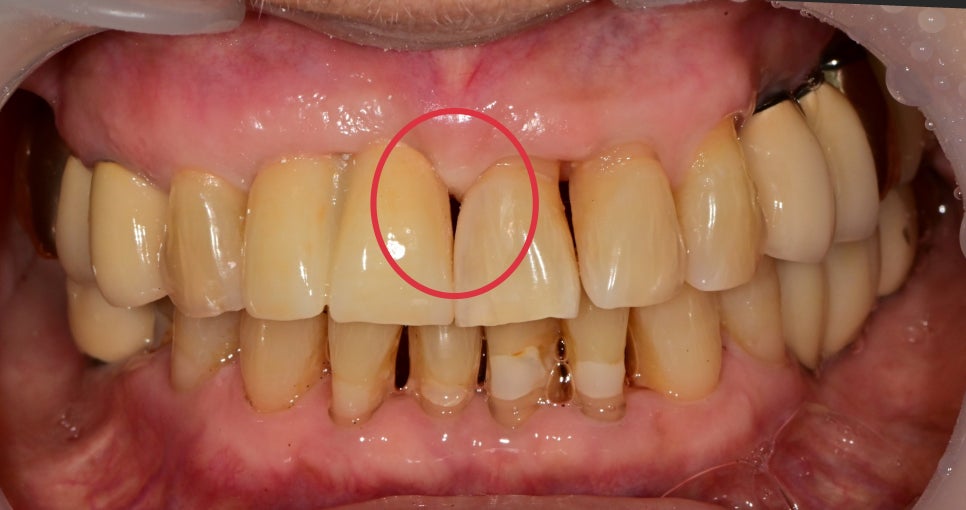

레진을 이용해 일단 대칭되는 치아를 빈 공간 쪽으로

풍융하게 형성해 준 후 임플란트 보철을 수정했습니다

이 경우는 기존 치아가 얇은 편이였기 때문에

빈 공간은 레진을 이용해서 채울 수 있었습니다

임플란트 보철 또한 대칭적으로 수정을 통해 빈 공간이 많이 채워졌습니다

아직 빈 공간이 남아있지만 저 부분은 시간이 지나면

자연스럽게 잇몸이 저절로 차오를 것을 기대해 볼 수 있습니다.